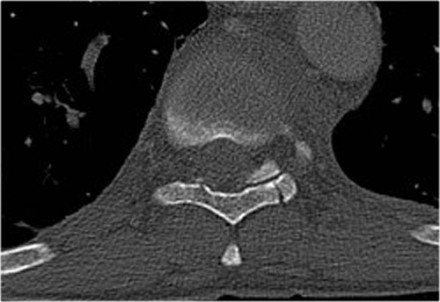

Case 4

Look at the images.

How would you describe the morphology and the PLC?

The findings are:

- Morphology: Distraction- 4 points

- PLC: always disrupted in distraction on posterior side - 3 points

- TLICS: 7 points

Case 6

Look at the images.

How would you describe the morphology and the PLC?

Then scroll to the next images.

The findings are:

- Morphology: Distraction - 4 points

- PLC: always torn in posterior distraction - 3 points

- TLICS based on imaging: 7 points

The key point in this case is that you should not describe this morphology as burst - 2 points.

The horizontal fractures on the posterior side and the increased

interspinous distance indicate distraction, which means a higher score

for morphology.

Always go for the highest possible score in TLICS.